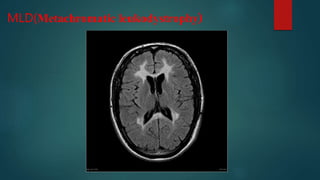

MLD(Metachromatic leukodystrophy)

• #49 Characterised by bilateral symmetrical confluent areas of periventricular deep white matter signal change, in particular around the atria and frontal horns with sparing of subcortical U fibres leading to a "butterfly pattern". Progression can lead to cortical and subcortical atrophy T2:affected areas are high signal and may show a "tigroid pattern" on axial plane or "leopard pattern" on sagittal plane representing sparing along the venules subcortical U-fibres are usually spared